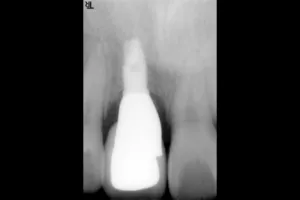

症例③

| 主訴 | 他院にて抜歯後、歯を入れたい |

| 診断名 | 歯根破折 |

| 年齢 | 46歳 |

治療に用いた装置(治療法) | 骨造成・インプラント |

| 部位 | 右上1 |

| 治療期間 | 8か月 |

| 治療費用 | 造成:55,000円 インプラント:462,000円 |

| リスク・副作用(治療に関する) | 腫服、しびれ |